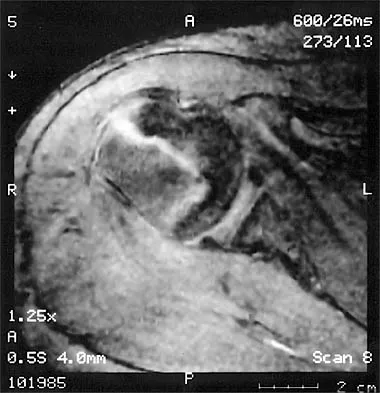

A 20-year-old patient has foot pain. A radiograph and T1-weighted MRI scan are shown in Figures 8a and 8b. A biopsy specimen is shown in Figure 8c. Treatment should consist of

Giant cell tumors occur near articular surfaces in young adults. The histology shows abundant giant cells with nuclei resembling the surrounding cells. Although the MRI scan shows soft-tissue involvement, curettage is still the preferred treatment. Chemotherapy is not necessary for benign lesions, and amputation is too aggressive. Cementation, phenol, and cryosurgery (liquid nitrogen) are all acceptable local adjuvants to curettage. Packing the cavity with bone graft rather than cement is also acceptable. Dahlin DC, Unni KK: Bone Tumors: General Aspects and Data on 8,542 Cases. Springfield, IL, Charles C. Thomas, 1986.